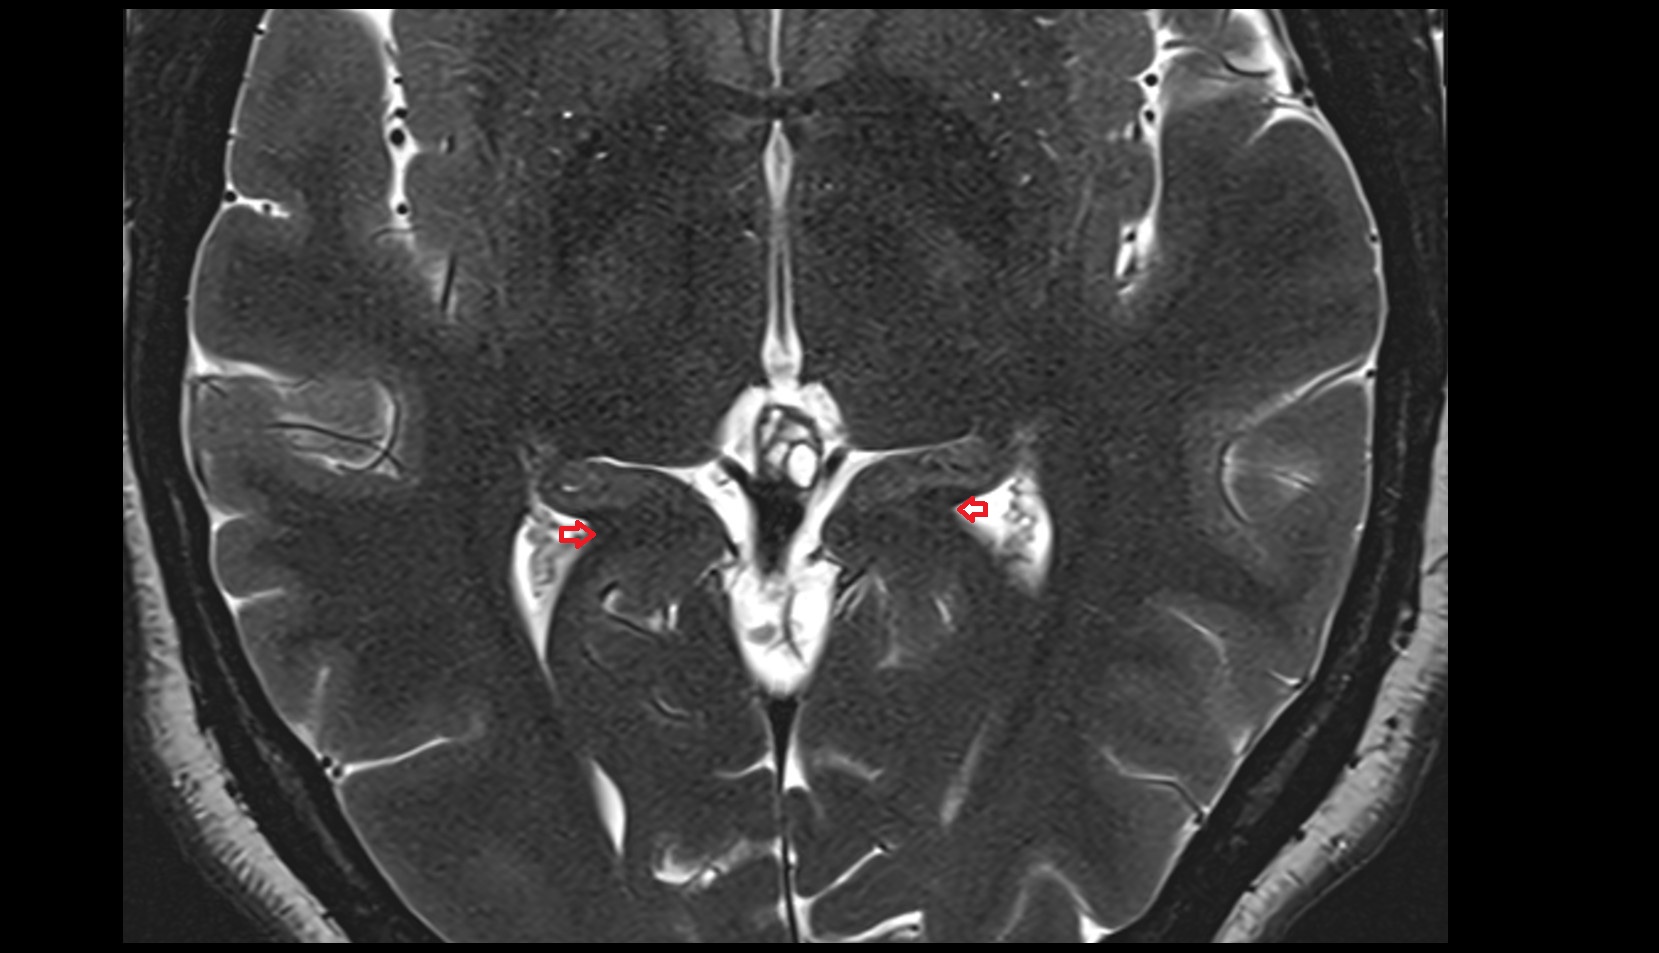

- Temporal horn of lateral ventricle

- Atrium of lateral ventricle

- Central part of lateral ventricle

- Frontal horn of lateral ventricle

- Occipital horn of lateral ventricle